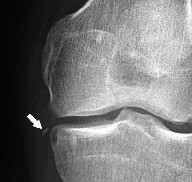

À la radiographie de face, la fracture de Segond présente l'aspect d'une pastille d’os située sur le bord supéro-externe du plateau tibial externe. Ce fragment peut toutefois être très difficile à discerner aux rayons X.